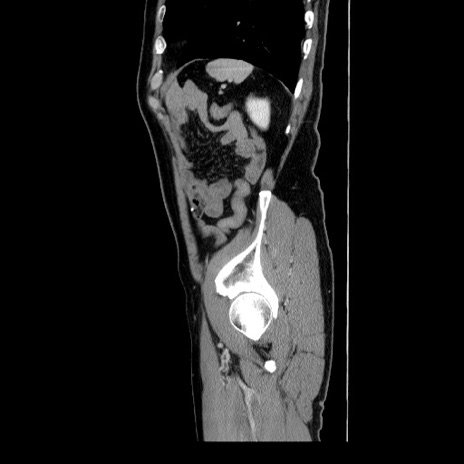

症例34(矢状断像)

【症例】60歳代 男性

【主訴】右鼠径部膨隆

【現病歴】1年程前より右鼠径部膨隆あり。自己にて還納可能だったため放置していた。3時間前より右鼠径部の脱出を認め、還納困難となり受診。

【身体所見】右鼠径部に小児頭大の膨隆あり。弾性硬であり、用手還納は困難。左鼠径部にも膨隆を認める。脱出はなし。